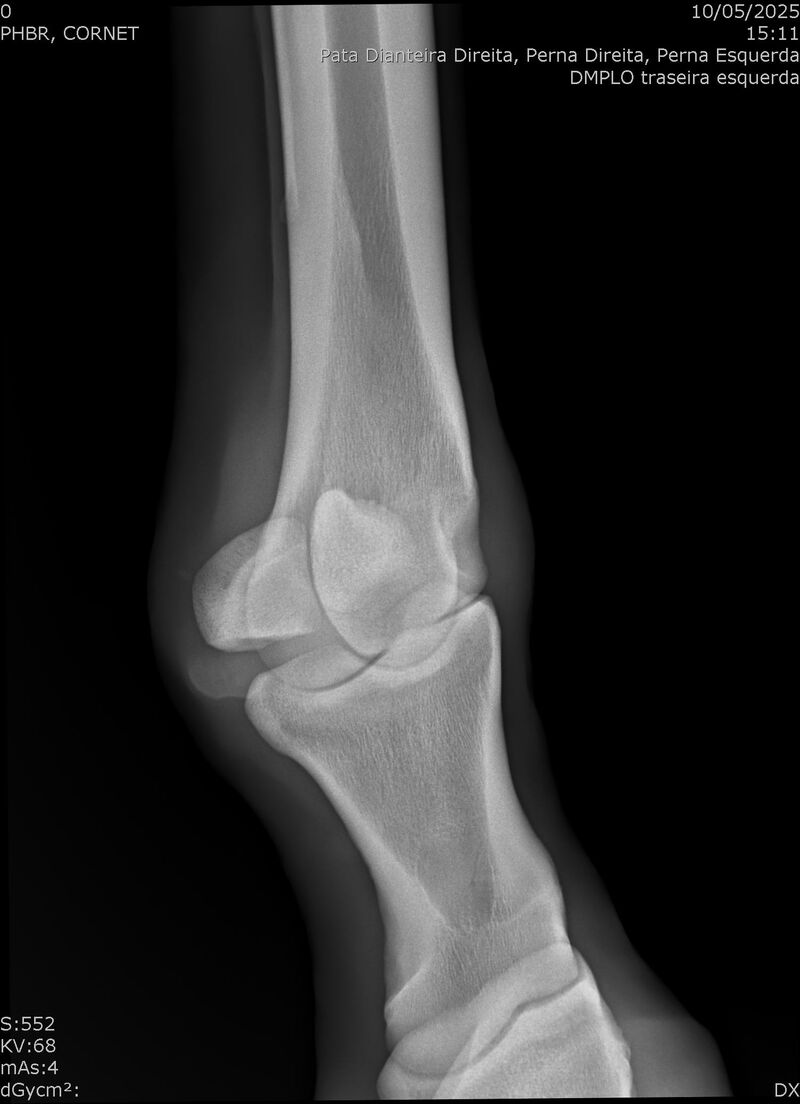

:: RAIOS-X DO LOTE